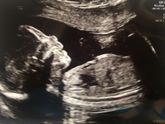

Божечки,как же иногда порой некоторые вещи даются с трудом ? Родился мой сладенький 8.12.17 в 11:08